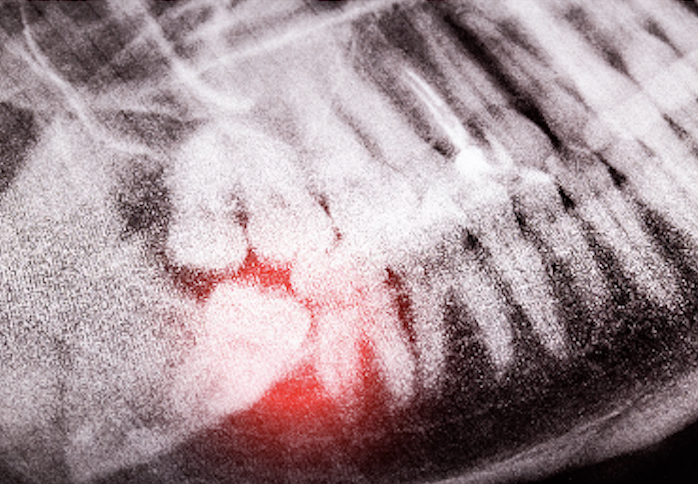

If the tooth is impacted, the dentist will make an incision in the gum tissue to expose the tooth and bone..

we will extract the wisdom tooth. In some cases, the tooth may need to be sectioned into smaller pieces for easier removal.